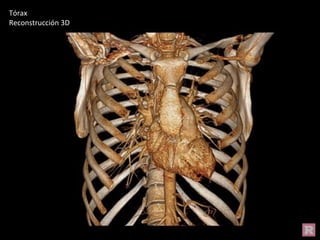

Tórax

Reconstrucción 3D